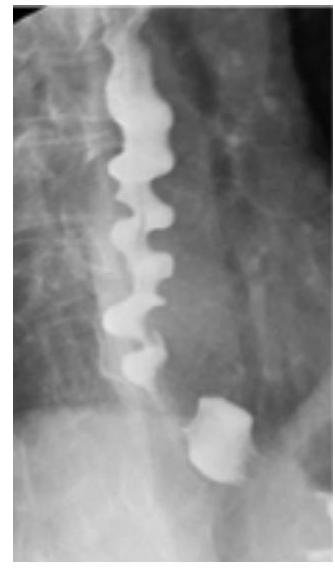

# OTROS TRASTORNOS DEL ESÓFAGO ## * 25-30 cm *LONG TUBE* from *PHARYNX* to the *STOMACH*  ## *FUNCTIONAL* - muscles & nerves - motility of the esophagus ## *MECHANICAL* - something within that blocks the passageway ## * WHAT TYPES OF FOODS PRODUCES THE SYMPTOMS - BOTH *LIQUIDS* & *SOLIDS* - **FUNCTIONAL** - *DYSPHAGIA* FOR ONLY *SOLIDS* - *LUMEN* IS NARROW - *MALIGNANCY* OR *STRICTURE* - CAN BE *INTERMITTENT* or *PROGRESSIVE* # ESPASMO ESOFÁGICO DIFUSO ## DEFINICIÓN Es un trastorno caracterizado por múltiples contracciones espontáneas o inducidas por la deglución, que son de comienzo simultáneo, de gran amplitud, de larga evolución y repetitivas. ## CLÍNICA  - **DOLOR TORÁCICO** (*generalmente retroesternal* y puede tener irradiaciones como cardiopatía) - **DISFAGIA** (*aparece tanto en sólidos y líquidos*, *intermitente* y *no produce pérdida de peso*) ## Edad Media de presentación: alrededor de 40 años. ## DIAGNÓSTICO - El esofagograma con bario y fluoroscopia puede evidenciar el típico **ESÓFAGO EN SACACORCHOS** (**CASCANUECES**) producido por las contracciones anómalas. - La Manometría es el mejor estudio para valorar. Se evidencia **hipertensión del EEI**, el cual se relaja durante las degluciones, a diferencia de la Acalasia.  **UNCOORDINATED HIGH-AMPLITUDE PERISTALTIC CONTRACTIONS**  ## TRATAMIENTO: - Fármacos - *relajantes de fibra muscular lisa* antes de las comidas (**nitroglicerina sublingual**, **dinitrato de isosorbide** y **calcioantagonistas** como **Nifedipino** y **diltiazem**). - **DILATACIÓN CON BALÓN** - **si falla el tratamiento farmacológico**. Dilata la parte inferior del esófago. Ayuda a la **disfagia**. - **Miotomía Longitudinal** - Si fallan los tratamientos anteriores, esta intervención en la capa muscular circular del esófago, junto con una técnica antirreflujo si la presión del *EEI* es baja. # ESÓFAGO ESCLERODERMIA ## DEFINICIÓN Existe una atrofia del músculo liso del esófago con debilidad en la contracción de los dos tercios inferiores del mismo e incompetencia del esfínter esofágico inferior. ## CLÍNICA ## **PRESENTE EN ENFERMEDAD MIXTA DEL TEJIDO CONJUNTIVO.** - Disfagia a sólidos y líquidos. - Disfagia persistente - Estenosis péptica. ## DIAGNÓSTICO - Manometría - Demuestra **disminución amplitud de las contracciones**. - Presión *EEI* basal disminuida, pero normal en deglución. - Endoscopia que evidencia atrofia de músculo. ## TRATAMIENTO - **No puede revertir las anormalidades motoras**. - Se enfoca en **paliar el reflujo y sus complicaciones**.  **HIGH SPECTRUM** **MANOMETRY** ## ANILLO DE SCHATZKI Se forma una banda mucosa delgada y simétrica, localizada en el esófago distal. - Se asocia a **presencia de hernia hiatal y esofagitis eosinofílica**. ## CLÍNICA - **Disfagia intermitente a sólidos**. ## DIAGNÓSTICO ## Esofagograma con bario - Se observa **dilatación en área afectada**.  # Endoscopia - Se observa **membrana delgada**. ## TRATAMIENTO - **Dilatación con balón**. ## DIVERTÍCULO DE ZENKER Son protrusiones de la mucosa faríngea a través de una zona relativamente débil de la pared posterior de la faringe. - Ubicado en la parte superior del músculo cricofaríngeo. - Ocurre con más frecuencia en masculinos ancianos. ## CLÍNICA - Disfagia orofaríngea intermitente. - Halitosis por acumulación de restos. - Regurgitación. - Aspiración pulmonar. - Puede ser palpado a la EF. ## DIAGNÓSTICO - Esofagograma con Bario. - Se observa el divertículo. - **NO ENDOSCOPIA POR RIESGO DE PERFORACIÓN**. ## TRATAMIENTO - **Corrección quirúrgica**.  # PÓLIPO ESOFÁGICO ## DEFINICIÓN Los pólipos fibrovasculares del esófago son tumores benignos raros, caracterizados por el desarrollo intraluminal de una masa pedunculada de localización principal en el esófago cervical a nivel cricofaríngeo, no produce molestias por largo tiempo, sin embargo, puede ocurrir la regurgitación del pólipo, produciendo asfixia o **más FRECUENTEMENTE DISFAGIA**. ## CLÍNICA A pesar de su gran tamaño y potencial crecimiento, la transformación maligna es bastante rara. Usualmente crecen en el tercio proximal y permanecen asintomáticos por largo tiempo. Cuando son sintomáticos, el cuadro clínico puede ser espectacular y a veces letal por **obstrucción de la vía aérea**. ## DIAGNÓSTICO Puede ser por tomografía computarizada y resonancia magnética cuando se analiza mediastino. La endoscopía permite una visualización directa y fácil para su diagnóstico y valoración. ## TRATAMIENTO Depende del tamaño del tumor; así, los pólipos menores de 2 cm pueden ser extirpados por endoscopía, sin embargo, en la mayoría de los casos, se requiere de la **escisión quirúrgica**.  # SÍNDROME DE MALLORY-WEISS Consiste en **hemorragia digestiva alta** que se produce como consecuencia de erosiones longitudinales en la región de la unión gastroesofágica. ## **RESULTADO DE INTENSOS VÓMITOS O INCLUSO TOS.** - Las lesiones se ubican en el lado gástrico de la unión gastroesofágica. - El sangrado cesa en el 80-90% espontáneamente. ## DIAGNÓSTICO **Endoscopia** (la cual puede ser terapéutica) ## TRATAMIENTO - **Embolización**. - Casos raros **cirugía**.  ## SÍNDROME DE BOERHAAVE Se trata de la rotura de la pared esofágica a consecuencia de vómitos de repetición. Provoca mediastinitis y complicaciones de la misma. ## ETIOPATOGENIA 1. **Aumento repentino de la presión interna del esófago** producida durante los vómitos intensos. 2. Consecuencia de una **falta de coordinación neuromuscular** que causa un fallo del cierre del músculo cricofaríngeo (el esfínter inferior del esófago). ## CLÍNICA - **Dolor retroesternal** (Mediastinitis)  ## DIAGNÓSTICO **ESOFAGOGRAMA**: se confirma hasta en 90% de los casos por la observación de extravasación de medio de contraste en el esofagograma. ## TRATAMIENTO - Antibióticos. - Reparación quirúrgica. **UBICACIÓN HABITUAL - PARED POSTERIOR DE LOS 2/3 INFERIORES DEL ESÓFAGO 2-3cm ANTES DEL ESTÓMAGO**